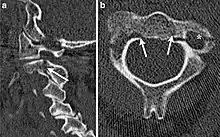

| CT scan of hangman's fracture | |

Hangman's fracture is the colloquial name given to a fracture of both pedicles, or partes interarticulares, of the axis vertebra (C2).[1]